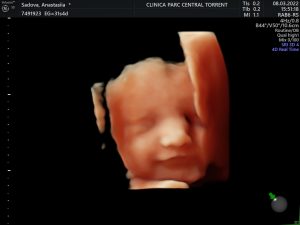

Imágenes asombrosas de tu bebé, captura cada detalle desde antes del nacimiento.

Nuestras ecografías permiten ver las emociones de tu bebé en la mejor calidad.

Somos un equipo especializado en imagen prenatal, ponemos a tu disposición espacios adaptados con la más alta tecnología en ecografías 5D y 4D en 8K, ahora tus ecografías con Hiperrealismo, al instante sin esperas.